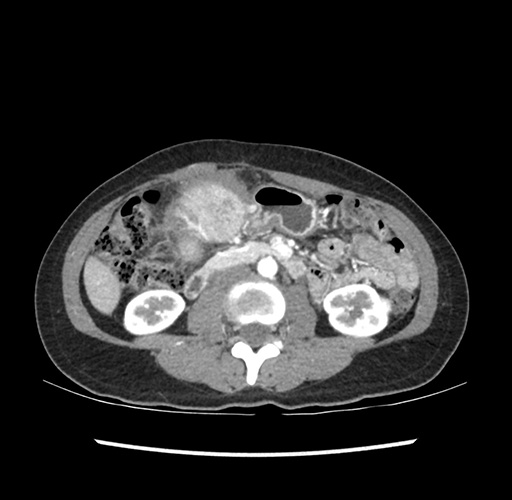

Imaging Analysis

Look through the patient's CT scan to identify any areas of concern for the necessary procedure.

Based on your CT findings, which issue(s) would give reason for "planned slowing down moment(s)" in this case?

Considering a standard left lateral sectionectomy procedure, what step(s) of the operation would you do differently in this case ?